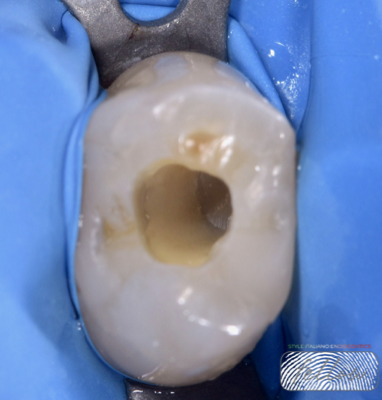

Fig. 3

Following local anesthesia, the pulp chamber was opened, revealing purulent exudate. Proper root canal shaping is crucial, particularly in necrotic teeth, as it allows irrigants to penetrate deeply, exert antimicrobial effects, and dissolve organic debris. Proper shaping also facilitates the effectiveness of sodium hypochlorite, enhancing pulp tissue dissolution and thorough canal cleaning.